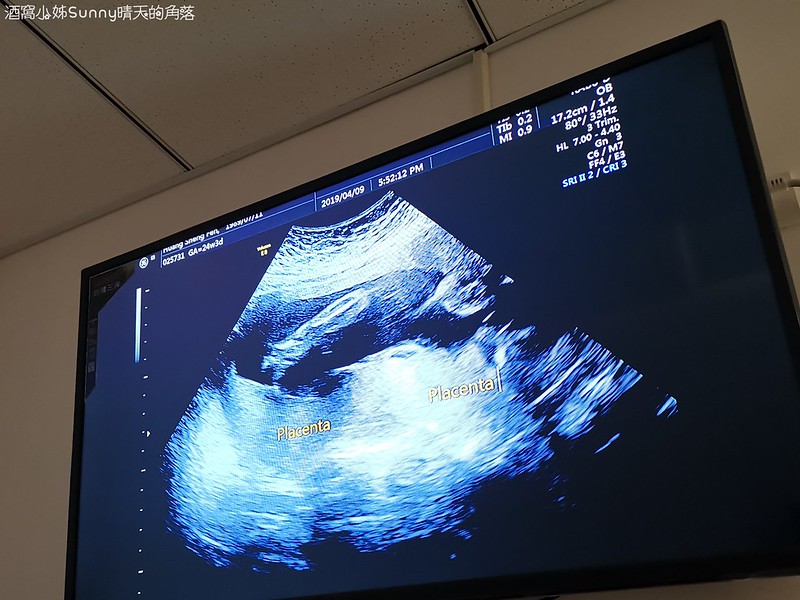

8. 胎盤位置

9. 羊水量

▼所以醫生在解釋的時候我們大概可以聽懂7~8成(下圖是胎盤,但不說一般人應該很難看懂吧!)